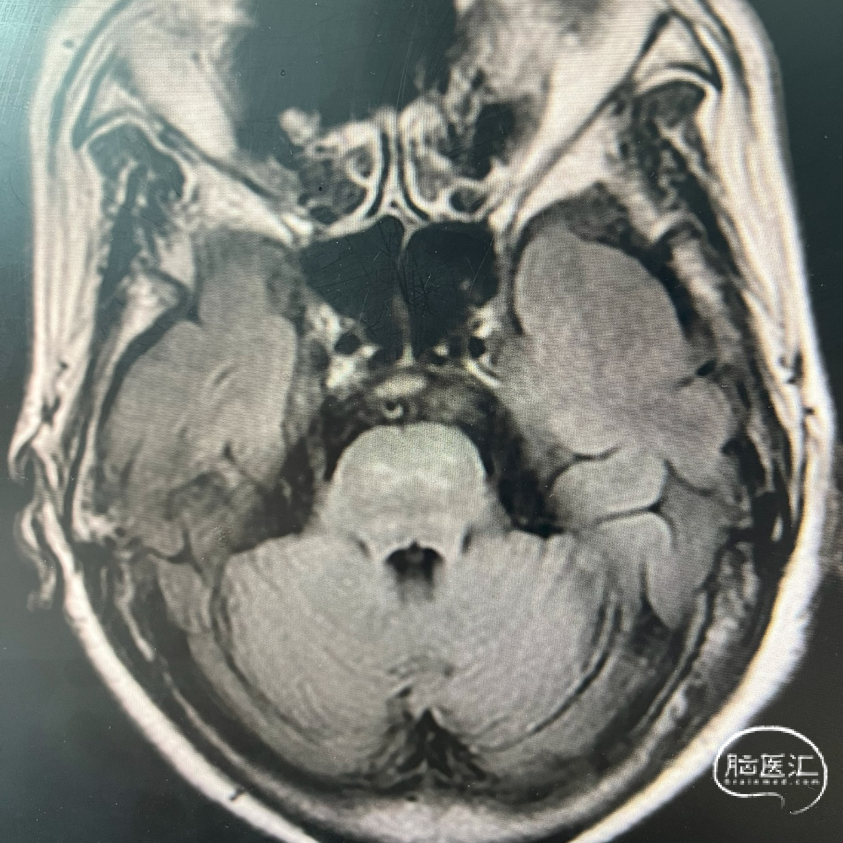

术前MRA

1、主动脉弓及其他弓上血管,III型弓,弓上血管迂曲,血管通畅。

2、颈内动脉系统:

右侧颈总动脉及颈内动脉血管通畅,远端右侧大脑中动脉血流通畅,可见同侧及对侧大脑前动脉显影。

左侧颈总动脉及颈内动脉血流通畅,后交通开放,可见同侧大脑后动脉显影,大脑前动脉血流通畅。

3、椎基底动脉系统:

右侧椎动脉优势型。

左侧椎动脉血管纤细,远端可见基底动脉浅淡显影。

右侧椎动脉优势型,远端汇入基底动脉。

基底动脉中段重度狭窄,狭窄率约80%,双侧大脑后动脉可见显影。